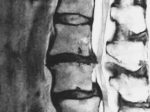

画像診断

MRI(磁気共鳴画像)、CT(コンピュータ断層撮影)、X線などの画像診断を使用して、坐骨神経や梨状筋周辺の異常を確認することがあります。